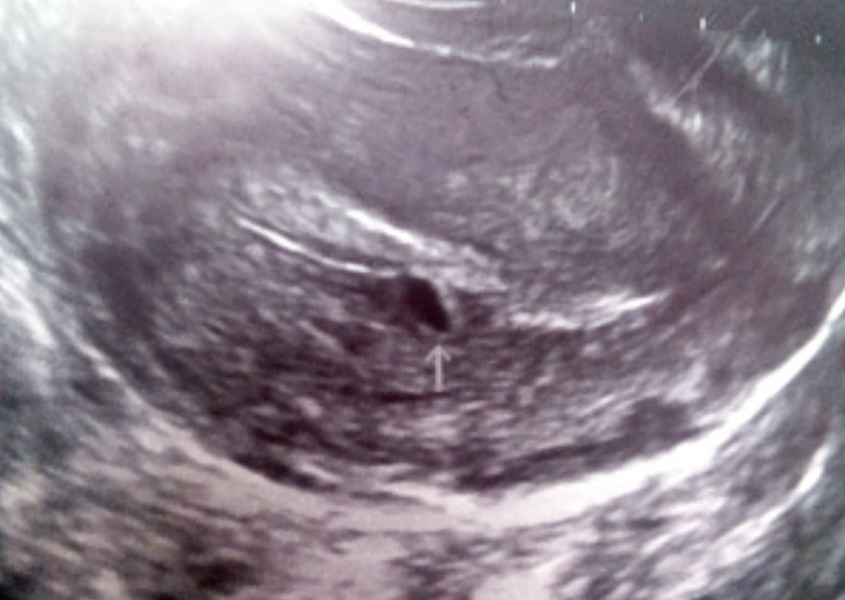

남편과는 대치동 위치한 독서논술 학원에서 강사 일을 하다가 만나 약 5년간 연애를 하고, 2013년에 결혼을 했다. 그리고 2014년에 첫 임신 소식을 받아 들었다. 여느 여성들처럼 '임테기'라고도 히 불리는 임신 테스트기의 선명한 두 줄을 확인하고 동네 산부인과에서 초음파 검진을 받았다.

연애 기간도 길었겠다, 슬슬 아이가 생겨도 좋겠다고 생각하고 피임약을 끊었을 즈음 자연스레 임신이 되었고, 남편과 함께 병원에서 초음파 사진으로 아기집을 확인했을 때에도 어디에선가 많이 본 듯한 감격스러은 한껏 뺀 그런 마음으로 우리 이제 부모가 되나 보다 생각했다. 그리고 곧바로 손주 소식이 퍽 궁금하셨을 양가 부모님께 연락을 드렸다. (초보 부부의 실수가 여기에 있었다...)

바로 다음 주 산부인과 검진에서 부정적인 소견을 들었다. 아기집은 보이는데 아기가 보이지 않는다고. 고사 난자일 확률이 높다면서 다음 주에도 배아가 확인되지 않으면 1~2주 안에 소파 수술을 진행해야 할 수 있다는 이야기였다. 임신 초기가 위험하다는 말은 익히 들었지만 이게 내 얘기일 줄은 몰랐지.